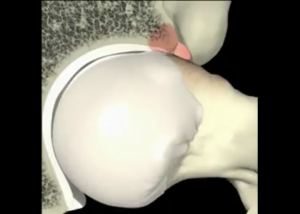

Le conflit fémoro-acétabulaire (CFA) est une condition complexe touchant l’articulation de la hanche, résultant d’un contact anormal entre le col du fémur et l’acétabulum. Cette

Le conflit fémoro-acétabulaire (CFA) est une condition complexe qui affecte l’articulation de la hanche. Il se caractérise par un contact anormal à l’intérieur de cette